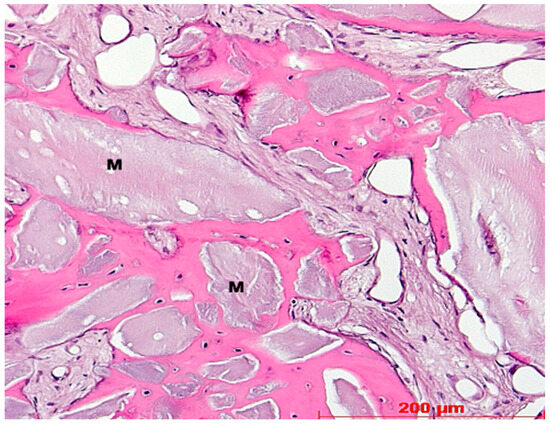

2.1. Histology

2.3. Histological Evaluation